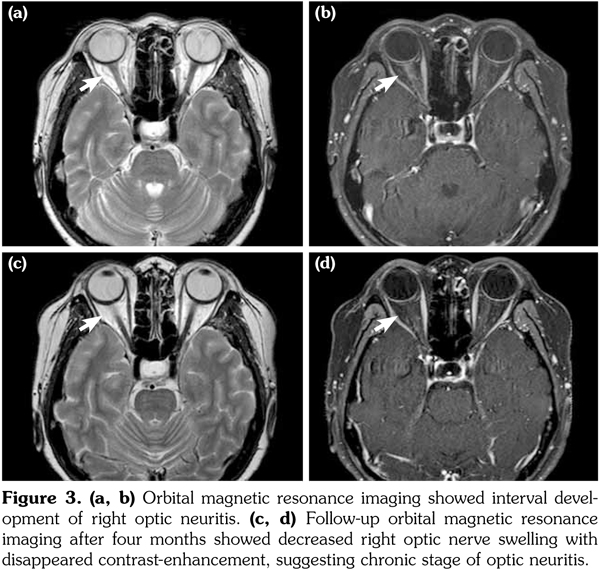

A 43-year-old female patient presented with acute-onset fever, headache, dysarthria, amnesia, left-side weakness, and dysesthesia. Initial brain computed tomography scans showed a 7 cm, mass-like lesion in the right frontoparietal region, suggesting a brain tumor. However, brain magnetic resonance imaging (MRI) revealed that

(a) the lesion was largely edema with high T2 signal intensity and no primary mass, accompanied by multiple small lesions in the corpus callosum and periventricular white matter (Figure 1). The cerebrospinal fluid profile showed the following: white blood count, 16/mm(3) and protein, 55 mg/dL. Considering the possibility of encephalitis, empirical antibiotics and acyclovir were administrated, but no improvements in her symptoms or MRI were observed. Under suspicion of tumefactive multiple sclerosis and other demyelinating diseases, intravenous steroid pulse (methylprednisolone 1 g) therapy for five days and subsequent high-dose prednisolone was administered. The patient recovered enough to walk and only a tingling discomfort remained in the left hand. She was referred to a rheumatologist to screen for underlying autoimmune diseases. She had complained of dry mouth for 10 years, but denied having dry eyes. Blood tests showed the following: positive for antinuclear antibody 1:320 (speckled pattern) and anti-SSA/Ro, and negative for anti-SSB/La, anti-double-stranded deoxyribonucleic acid, rheumatoid factor, and anti-phospholipid antibodies, with normal C3/C4 levels. Salivary scintigraphy showed decreased uptake in the submandibular and parotid glands (Figure 2a), and examinations for dry eyes were positive. A minor salivary gland biopsy showed lymphoplasmacytic infiltration with a focus score >2 (Figure 2b). Therefore, she was diagnosed as having pSS with CNS involvement in the form of tumefactive encephalitis. Monthly intravenous cyclophosphamide therapy was started and glucocorticoids were tapered slowly. A written informed consent was obtained from the patient.